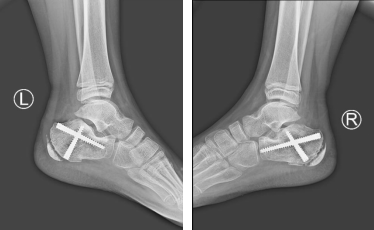

术后

经过一周的消肿后,徐明亮主任魏笛医生手术小组按计划给小吉进行了踝关节镜辅助下撬拨复位内固定手术。

手术中,医生在患者足跟外侧切0.5厘米左右小口,踝关节镜由此进入,距下关节在镜下暴露得非常充分,手术医生凭借清晰的视野,精确地复位骨折。